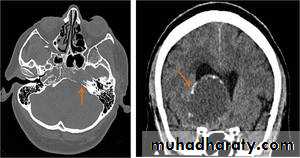

Posterior fosse tumor

Medullo blastomaAge incidence between 5-15 Y represent about 35-40 %of PFT

Arise from the midline mainly within or from the roof of the 4 TH ventricle fill the fourth ventricle & seeding via the csf so can seen in the distal part of the spinal canal .

CT finding as well circumscribed lesion heterogeneous in density ,have solid & cystic part , with also scattered calcification little surrounded edema , the solid part is enhance

90 % present with obstructive hydrocephalous at the level of the 4Th V. with dilatation of the lateral V. ( body , frontal , temporal & third ventricle )

40 % of child have secondary metastasis at the time of presentation